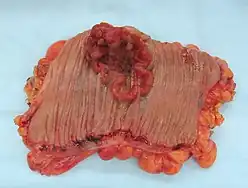

Cancer

Small bowel or colon cancer may require surgical resection.[7]

Small bowel cancer often presents late in the course due to non-specific symptoms and has poor survival rates. Risk factors for small bowel cancer include genetically inherited polyposis syndromes, age over sixty years, and history of Crohn's or Celiac disease. Cases that present before stage IV show survival benefit from surgical resection with clear margins. It is recommended that surgical resection also include lymph node sampling of a minimum of 12 nodes with some groups extolling more extensive resection. When evaluation determines cancer to be stage IV, surgical intervention is no longer curative, and is only used for symptom relief.[7]

Colon cancer is the third most common cancer and the second most common cause of cancer death in the USA.[8] Due to its prevalence, screening protocols have been created for prevention of disease. Screening colonoscopies with or without polypectomy have been shown to decrease cancer morbidity and mortality.[9] When cancer is more advanced and polypectomy is not possible surgical resection is necessary. Using imaging and pathologic evaluation of resected tissue the tumor may be staged using AJCC stages.[9] Surgical resection of tumors for staging and for curative purposes requires removal of local blood vessel and lymph nodes. Standard lymph node resection includes three consecutive levels of lymph nodes and is known as a D3 lymphadenectomy.[10] In addition to surgery adjuvant chemotherapy may be used to decrease risk of recurrence. Chemotherapy is standard with stage III cancer, case dependant in stage II and palliative in stage IV.[11] Diet high in processed food and sugary drinks has also been shown to increase recurrence of stage III colon cancer.[12]